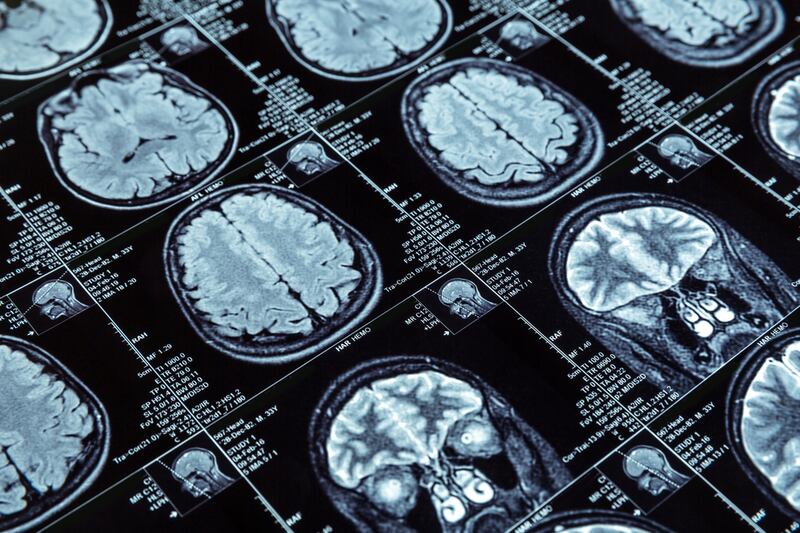

¿Qué es una embolia?

Una embolia es una condición médica grave que ocurre cuando un coágulo de sangre u otra sustancia bloquea el flujo de sangre en un vaso sanguíneo, impidiendo que el oxígeno y los nutrientes lleguen a los tejidos afectados.

Según el Instituto Nacional de Salud de Estados Unidos (NIH, por sus siglas en inglés), este bloqueo puede presentarse en cualquier parte del cuerpo, aunque es más frecuente en el cerebro (embolia cerebral) o los pulmones (embolia pulmonar).